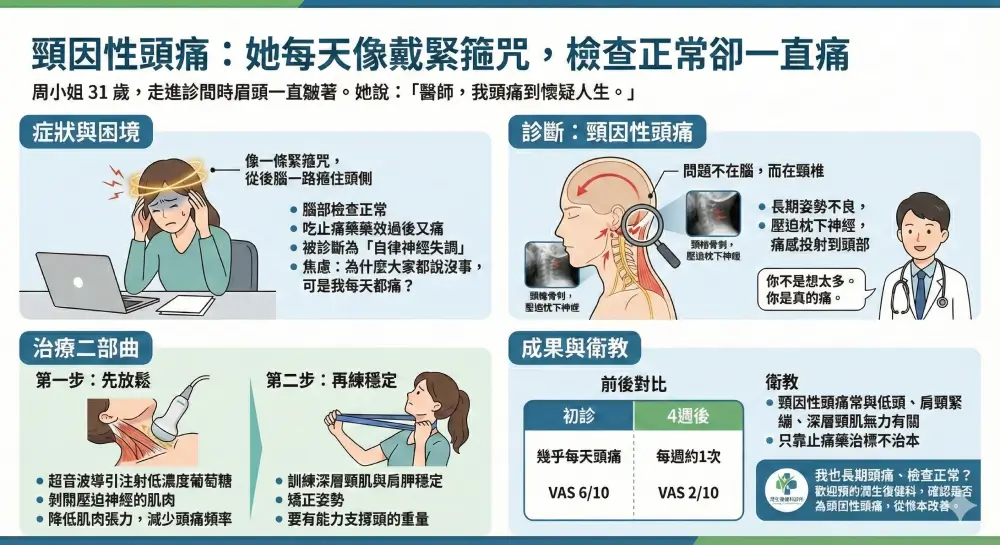

頸源性頭痛 (1)